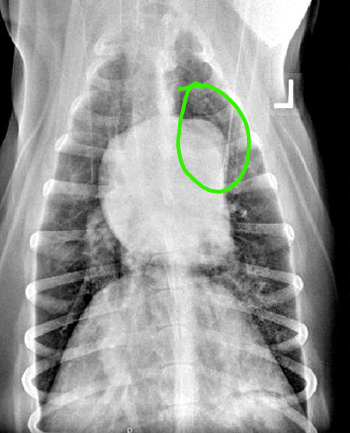

VD

DV